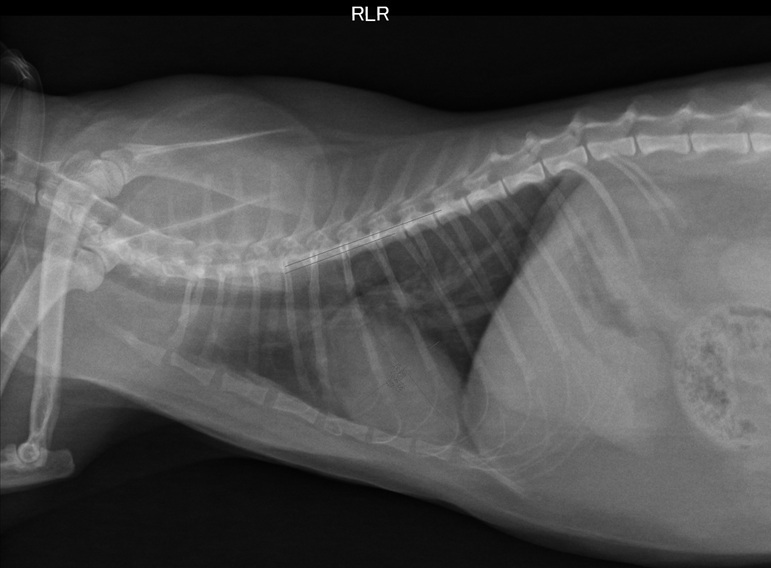

8/3回診- 4.45kg

罔市離上次回診已過了半年,

為確認目前的心臟狀況而回診做各項檢查。

檢查項目有測血壓140 (正常),

拍X光照片和心電圖超音波,

醫生認為心臟狀況看起來還不錯,

但目前還是需要持續服用心臟藥以維持正常的機能,

不過活動方式都可以繼續和之前一樣,

有照護員在時可讓罔市出籠活動活動。

醫生認為罔市之後是可能有可以停藥的一天,

不過要視之後回診的檢查結果作評估,

下次回診為半年後。